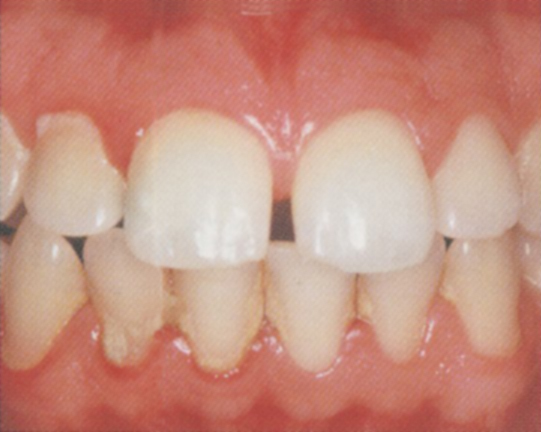

Zánět dásní (gingivitis) obr. 2

- dásně jsou zduřelé a zarudlé

- při čišťění dásně krvácí

- objevuje se zvýšená citlivost

- pocit zápachu z úst